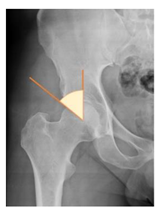

| Lateral center-edge angle (lcea) | The angle measured between two lines drawn from the center of the best fit circle for the inferior and medial margins femoral head, one running vertically along the longitudinal axis of the pelvis and the other to the lateral acetabular rim [23,24] | 25–39° | ![]() |